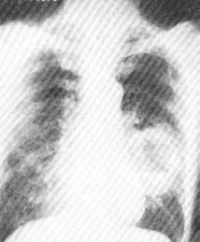

1、X线检查

X线检查是诊断肺癌最常用的重要手段。通过X线检查可以了解肺癌的部位和大小。早期肺癌病例X线检查虽尚未能显现肿块,但可能看到由于支气管阻塞引起的局部肺气肿、肺不张或病灶邻近部位的浸润性病变或肺部炎变。